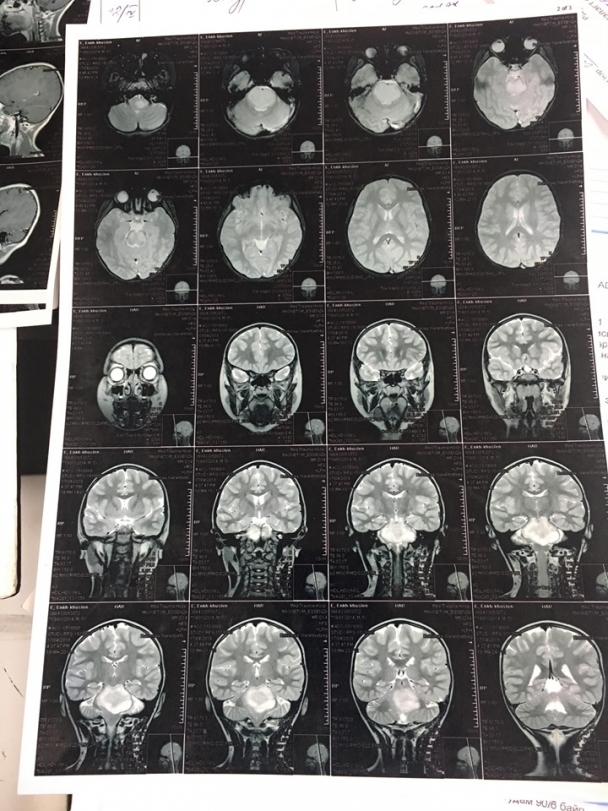

Э.Энхмарад охины ээж Н.Оюунтуяа хэлэхдээ " Охин минь 5 настай. Өмнө нь эрүүл саруул, сэргэлэн цовоо охин байсан. Энэ жилийн гуравдугаар сарын эхээр өвчин нь илэрч эхэлсэн. Юм ярихад ойлгохгүй болж, шүлс нь гоожоод л, нэг талын хөл нь хазайх зэрэг шинж тэмдэг илэрсэн. Эхлээд бид сэтгэцийн эмчид үзүүлэхэд сэтгэц биш гэсэн. Дараа нь ЭХЭМҮТ-ийн мэдрэлийн эмч н.Туулд үзүүлэхэд нэг талаараа тархины хавдар эсвэл саажилт явагдаж байна гэсэн. Ингээд MRI зураг авахуулахад тархины хавдар байсан.

Хавдар дундаа 1000-д нэг тохиолддог хүний уртавтар тархинд байдаг мэдрэлийн судас дарсан хорт хавдар байсан.